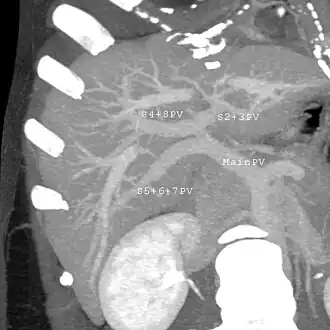

A CT scan in which the liver and portal vein are shown

With the recent advances of noninvasive imaging, living liver donors usually have to undergo imaging examinations for liver anatomy to decide if the anatomy is feasible for donation. The evaluation is usually performed by multidetector row computed tomography (MDCT) and magnetic resonance imaging (MRI). MDCT is good in vascular anatomy and volumetry. MRI is used for biliary tree anatomy. Donors with very unusual vascular anatomy, which makes them unsuitable for donation, could be screened out to avoid unnecessary operations.

MDCT image. Portal venous anatomy contraindicated for liver donation -